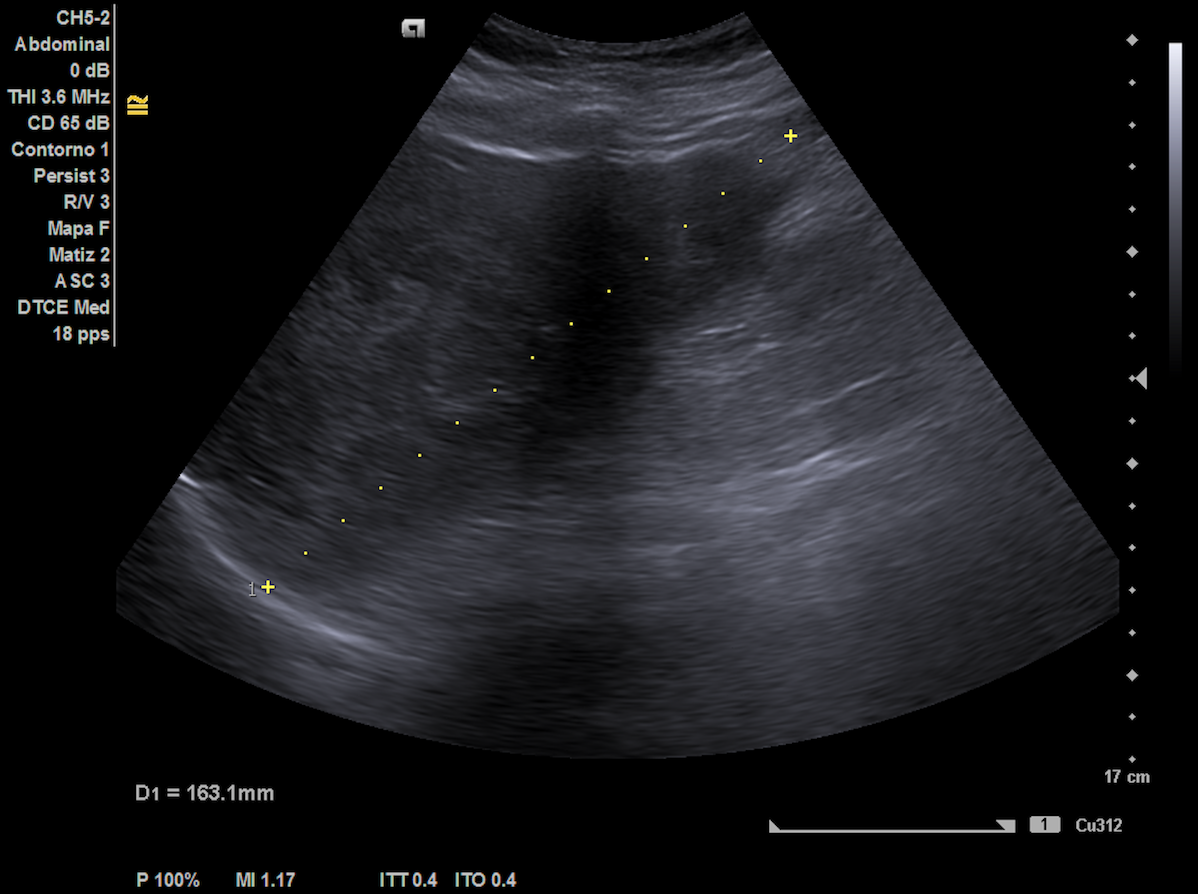

Exploración física: abdomen distendido moderadamente depresible, no doloroso a la palpación. Hepatomegalia con percusión timpánica de ascitis. En miembros inferiores, edemas hasta tercio tibial medio-proximal sin signos de trombosis venosa profunda y pulsos presentes. Ante esto, se decide realizar ecografía abdominal en ese momento, cuyos hallazgos motivaron la derivación a urgencias.

Ecografía hepática: hígado de tamaño normal con ecoestructura heterogénea, lesiones focales con halo hipoecoico en ambos lóbulos, sugerentes de metástasis. Las imágenes ecográficas del ingreso coincidían con nuestra descripción.